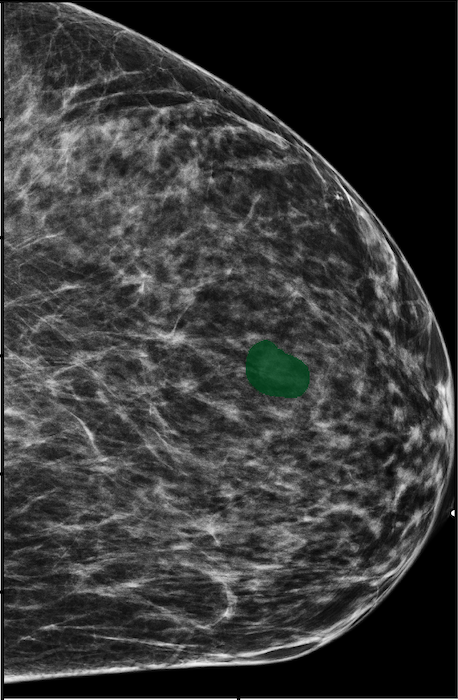

The NYU Breast Cancer Screening Dataset [78] includes 229,426 exams (1,001,093 images) from 141,472 patients.222Our retrospective study was approved by our institutional review board and was compliant with the Health Insurance Portability and Accountability Act. Informed consent was waived. Each exam contains at least four images which correspond to the four standard views used in screening mammography: R-CC (right craniocaudal), L-CC (left craniocaudal), R-MLO (right mediolateral oblique) and L-MLO (left mediolateral oblique). An example is shown in Figure 3.

Across the entire dataset (458,852 breasts), malignant findings were present in 985 breasts () and benign findings in 5,556 breasts (). All findings are confirmed by at least one biopsy performed within 120 days of the screening mammogram. For the remaining screening exams that were not matched with a biopsy, we assigned labels corresponding to the absence of malignant and benign findings in both breasts. In each exam, the two views of the same breast share the same label.

For all exams matched with biopsies, we asked a group of radiologists (provided with the corresponding pathology reports) to retrospectively indicate the location of the biopsied lesions. This way we obtained the segmentation labels: where if pixel belongs to the benign/malignant findings. An example of such a segmentation is shown in Figure 3. In all experiments (except for experiments in Section 3.6 that assess the benefits of utilizing segmentation labels), segmentation labels are only used for evaluation. We found that, according to the radiologists, approximately of exams were mammographically occult, i.e., the lesions that were biopsied were not visible on mammography, even retrospectively, and were identified using other imaging modalities: ultrasound or MRI.